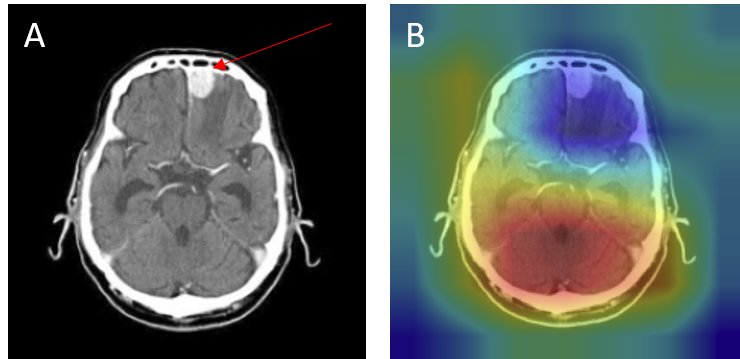

Although the model demonstrated high overall accuracy, systematic error analysis revealed several recurring failure modes. Examination of misclassified cases with Grad-CAM overlays provided critical insights into the underlying causes of these errors. In the figures presented below, red arrows denote the ground-truth lesion locations, allowing direct comparison between the true pathology and the regions emphasized by the model’s attention maps.

• Attention drift - Grad-CAMs sometimes highlight irrelevant regions such as skull edges or ventricles rather than the tumor mass (Figure 12B).

• Figure 12: Misclassification — meningioma as pituitary: (A) original with red arrow marking lesion, (B) Grad-CAM showing off-target attention.

Misclassifications

• Peripheral tumors - Lesions at the brain-skull interface, especially meningiomas, were occasionally misclassified as no tumor. Strong boundary contrast dominated the model's attention, while the actual lesion (red arrow) was ignored (Figure 13).

• Figure 13: Meningioma at brain-skull interface misclassified as no_tumor (false negative): (A) original with lesion marked by arrow, (B) Grad-CAM showing edge-dominated focus.